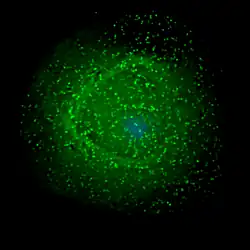

| Scanning electron micrograph of HIV-1 (in green) budding from cultured lymphocyte. Multiple round bumps on cell surface represent sites of assembly and budding of virions. | |